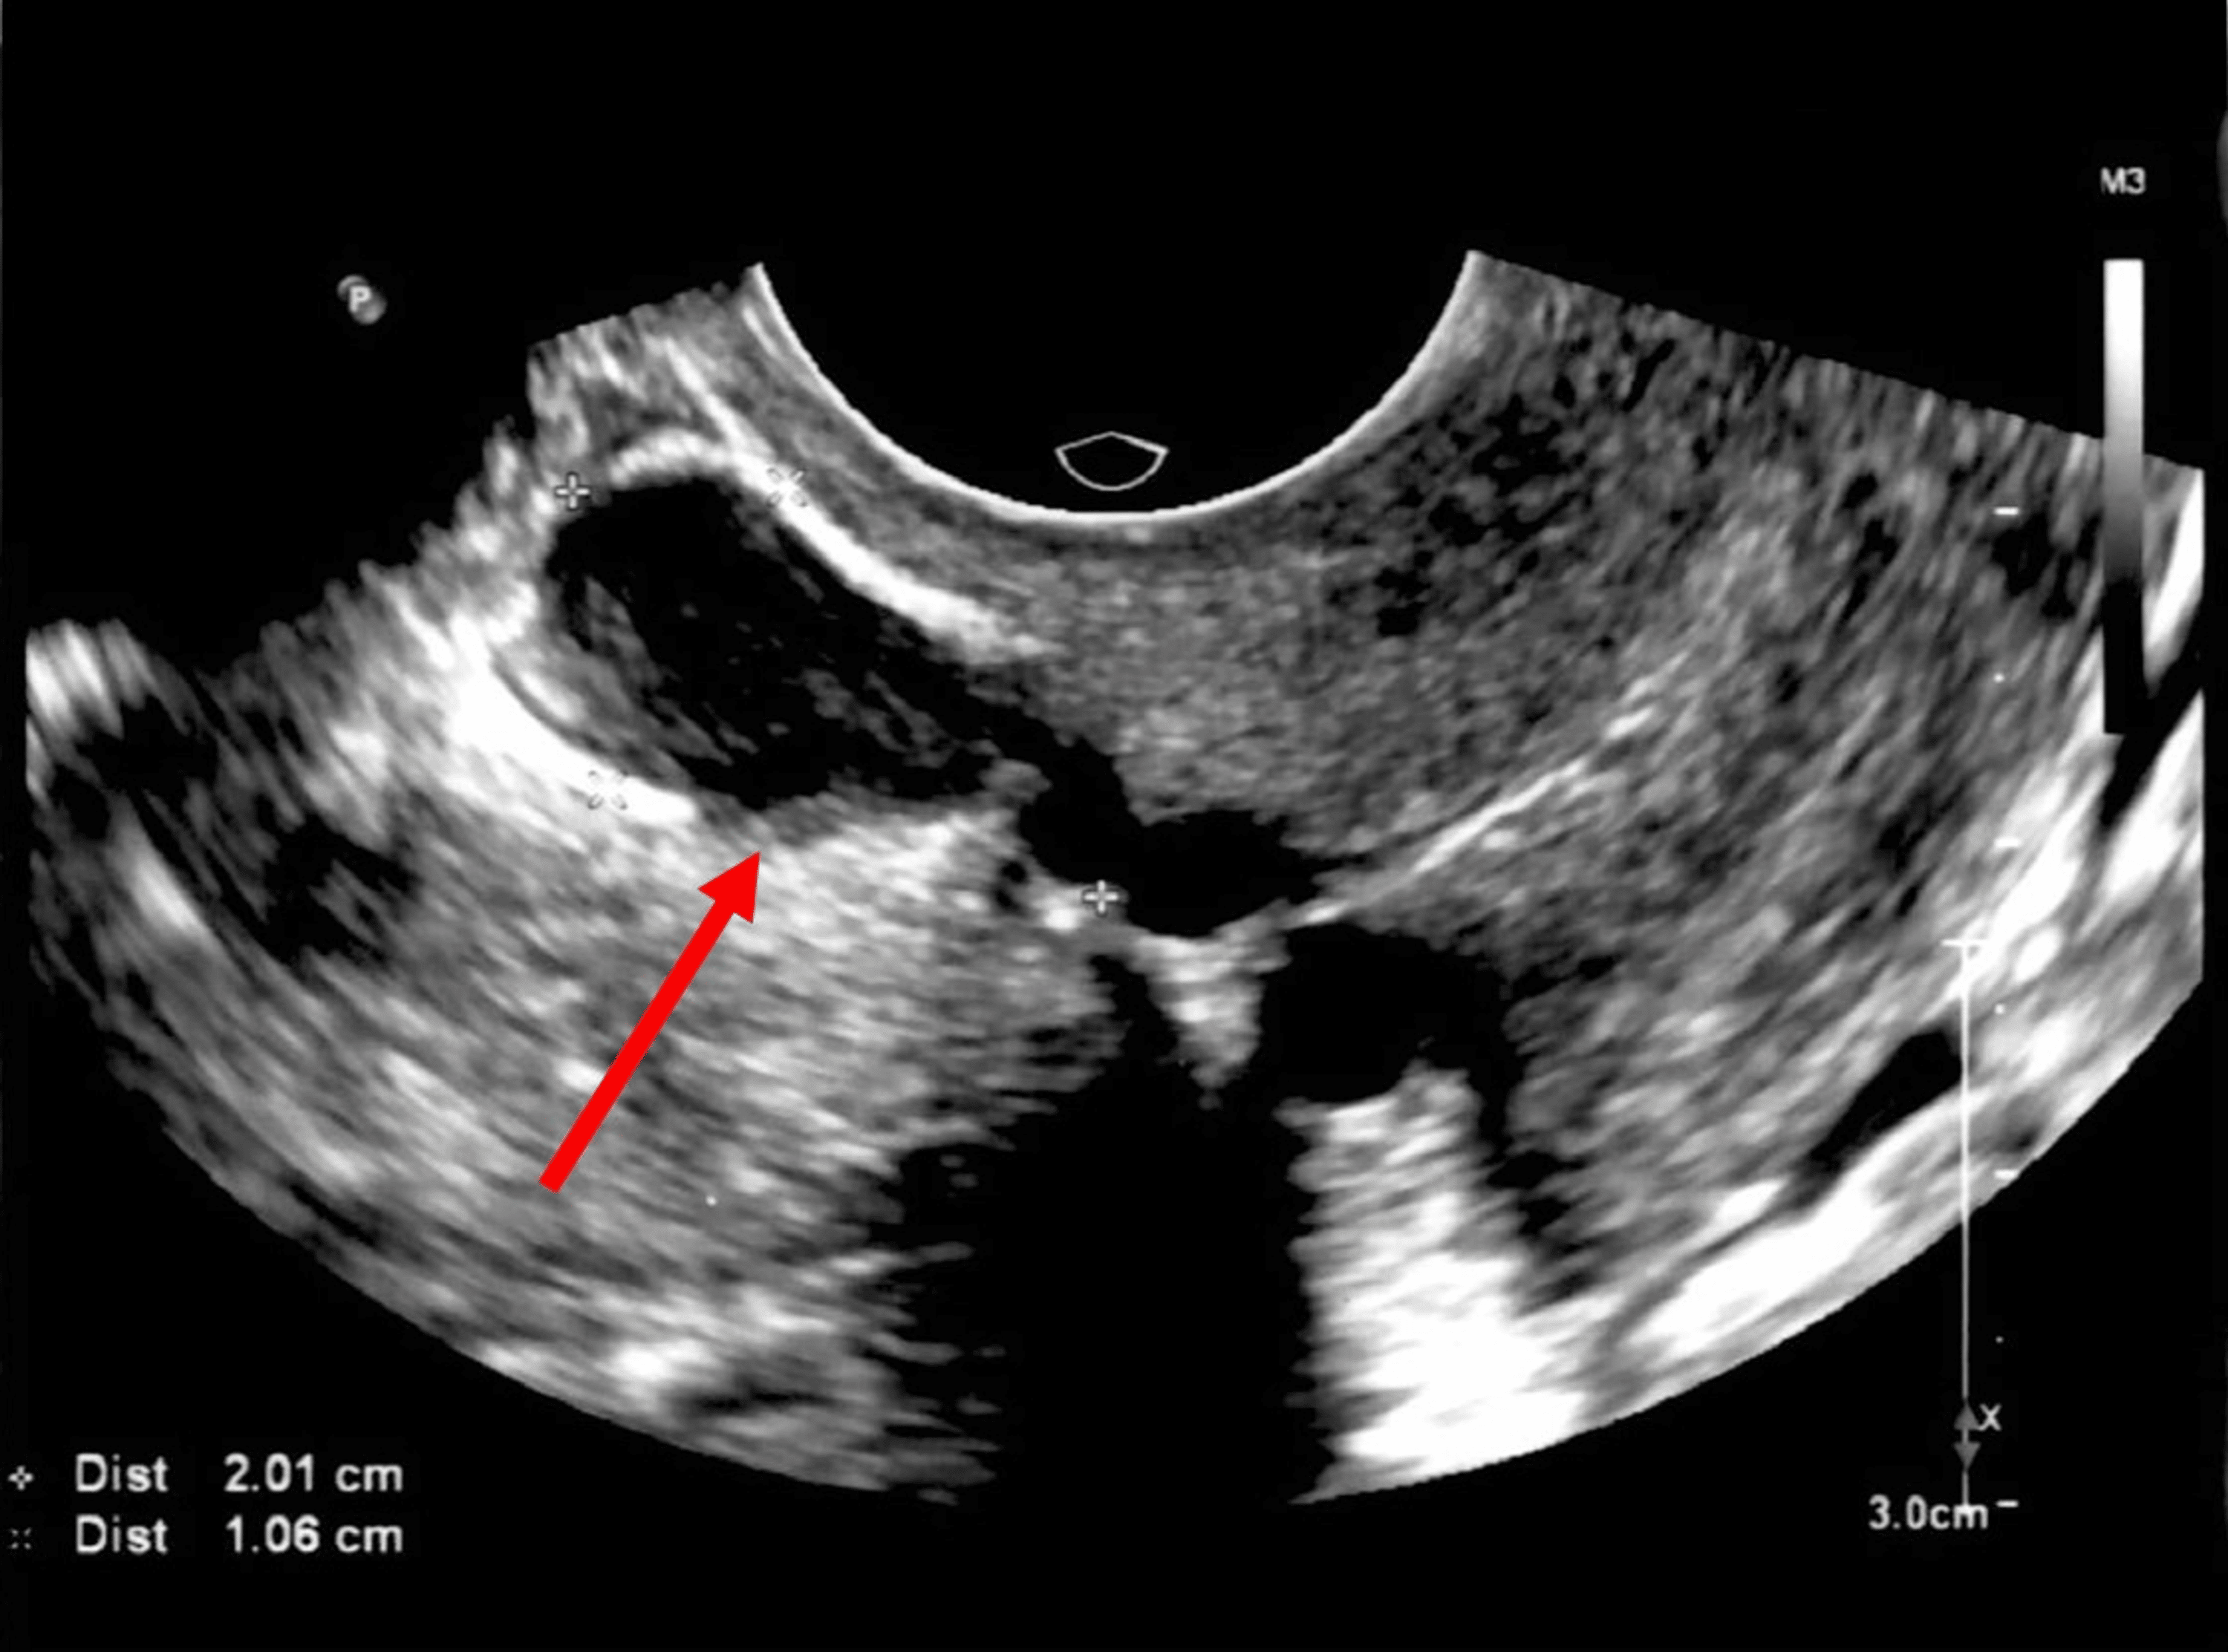

Cesarean scar niche 2D vaginal ultrasound. Download Scientific Diagram C Section Scar Endometriosis Treatment We report our experience in managing cesarean scar endometriosis (cse). Caesarian scar endometriosis can be located in the skin, subcutaneous tissue, rectus muscle/sheath, intraperitoneally, or in the uterine myometrium (within uterine. Treatment for endometriosis usually depends on your. Concerning the rising caesarean section rate, scar endometriosis may occur more frequently than generally assumed; Doctors may choose medical treatments, surgery, or. C Section Scar Endometriosis Treatment.

Fluidfilled cesarean scar niche Image C Section Scar Endometriosis Treatment Caesarian scar endometriosis can be located in the skin, subcutaneous tissue, rectus muscle/sheath, intraperitoneally, or in the uterine myometrium (within uterine. Concerning the rising caesarean section rate, scar endometriosis may occur more frequently than generally assumed; Treatment for endometriosis usually depends on your. We report our experience in managing cesarean scar endometriosis (cse). Doctors may choose medical treatments, surgery, or. C Section Scar Endometriosis Treatment.